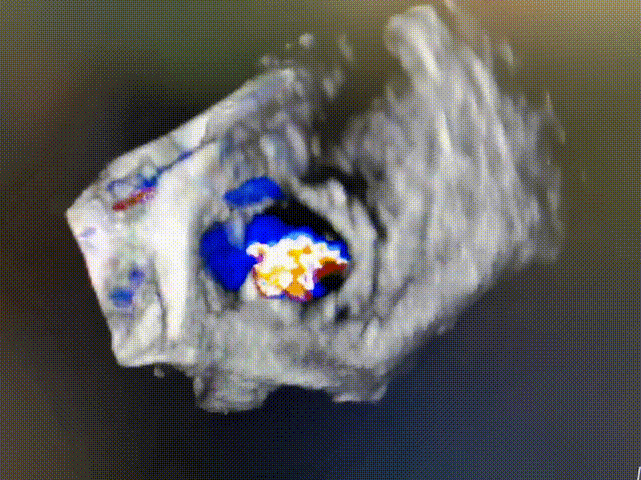

术前食道超声显示:三尖瓣成形术后表现,重度中心性三尖瓣反流,考虑右心室扩大牵拉三尖瓣腱索所致,瓣口面积4.0cm²。

术前三尖瓣重度反流